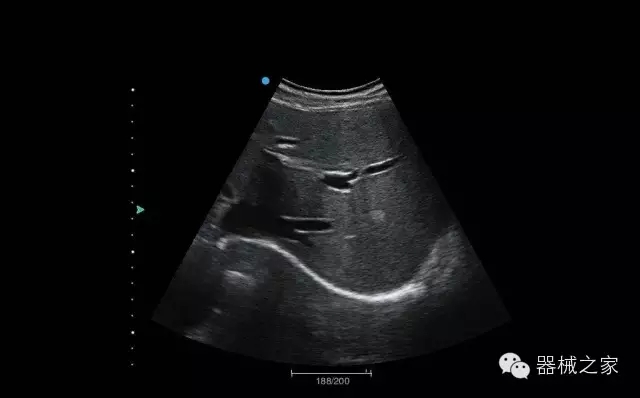

品牌:汕頭超聲(SIUI)

公司簡介:

總部位于廣東省汕頭經(jīng)濟特區(qū)的汕頭市超聲儀器研究所有限公司(SIUI)創(chuàng)建三十多年來,一直專注于醫(yī)學(xué)影像系統(tǒng)及工業(yè)檢測設(shè)備的研發(fā)和制造。

今天,SIUI已成為集醫(yī)學(xué)超聲顯像診斷系統(tǒng)、醫(yī)用X射線影像系統(tǒng)、工業(yè)檢測設(shè)備的研發(fā)、制造和銷售于一體的國家重點高新技術(shù)企業(yè)。

官方網(wǎng)站:www.siui.com

經(jīng)典產(chǎn)品:Apogee 1000

臨床圖片賞析

結(jié)甲

腎臟血流

肝血管瘤

產(chǎn)品特點

·屏幕可左右90度旋轉(zhuǎn);

·雙模操控;

·兩用提手;

·雙鋰電池;

·超輕機身;

·15寸高亮高清醫(yī)學(xué)顯示器;

·衛(wèi)星布局操控面板;

·一體化剪切板;

·多功能導(dǎo)航鍵;

“宏云”平臺

·采用移植自高端臺式彩超的“宏云”平臺技術(shù),使系統(tǒng)具有更優(yōu)秀的圖像效果;

人性化的設(shè)計

·內(nèi)置電池,輕巧的外觀設(shè)計以及臨床功能、軟硬件設(shè)計的人性化設(shè)計,使系統(tǒng)在臨床多科室移動診查中,均從容應(yīng)對;

Fusion THI二代融合諧波成像

·在不同諧波頻率段獲得的信息進行實時融合,既能獲得諧波圖像分辨率又能提高圖像的穿透力,降低圖像噪音;

XBeam多域復(fù)合成像

·通過頻域和空域角度進行復(fù)合的圖像處理,能有效消除由于圖像離散化和圖像衰減引起的空間分辨率下降的不利影響,彌補原有圖像空間分辨率的不足,獲得更加清晰的圖像;

CFDA注冊證編號

·粵食藥監(jiān)械(準(zhǔn))字2014第2231316號